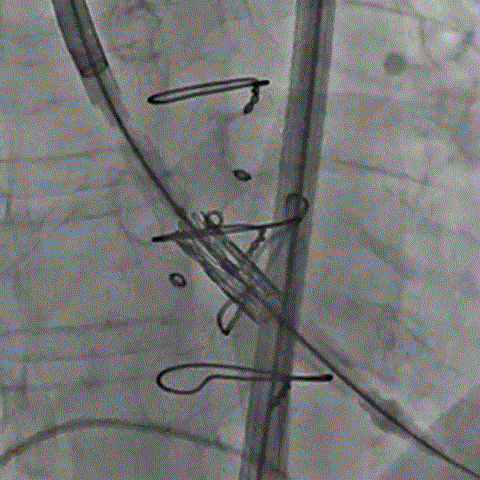

术前经详尽评估患者病情,通过CT重建测量瓣环直径、左室流出道面积。考虑到之前经房间隔入路外科换瓣,房间隔瘢痕严重,最终采用经心尖途径植入25# Renato球扩式瓣中瓣。手术顺利,瓣中瓣植入位置理想,功能表现出色,二尖瓣峰值流速由术前2m/s下降至1.4m/s,平均跨瓣压差由术前10mmHg下降至2mmHg,左室流出道压差正常,经食道超声观察无明显瓣中及瓣周返流。

术前经详尽影像学重建和评估,CT重建测量瓣环直径,评估冠脉梗阻风险及外周血管条件。最终采用经股动脉入路植入21# Renato球扩式瓣中瓣。手术顺利,瓣中瓣植入位置理想,功能表现出色,主动脉瓣峰值流速由术前4m/s下降至2m/s,平均跨瓣压差由术前40mmHg下降至6mmHg。经食道超声观察无瓣周漏及瓣中反流。